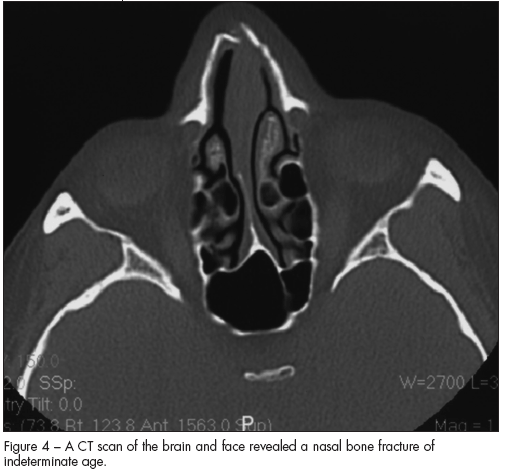

A head CT scan showed a displaced fracture of the distal tip of the right nasal bone (Figure 4). The fracture was of indeterminate age.

• Evidence or a history of previous injuries-possibly in different stages of healing. In this woman, for example, her nasal fracture was probably the result of an earlier assault.